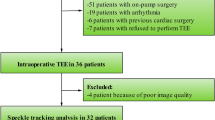

The St. Michael’s Hospital Research Ethics Board approved the protocol (September 2015). Eligible patients were approached preoperatively and written informed consent was obtained prior to conducting any procedures related to the study. Twenty-four patients undergoing elective CABG at St. Michael’s Hospital, Toronto were recruited from September 2015 to December 2015. Patients were excluded if they had a contraindication to TEE, left ventricular systolic dysfunction (defined as a left ventricular ejection fraction [LVEF] < 40% on preoperative transthoracic echocardiography), RV systolic dysfunction (defined as TAPSE < 17 mm on preoperative transthoracic echocardiography), previous cardiac surgery, hemodynamically significant valvular dysfunction (moderate or more stenosis/regurgitation of the tricuspid, pulmonary, mitral, or aortic valve), atrial fibrillation or flutter, or if they were < 18 yr of age, pregnant, or did not speak English.

In accordance with normal clinical practice, electrocardiogram monitoring was used for all patients, and a radial arterial cannula and pulmonary artery catheter (7.5 Fr, Edwards Lifesciences, Irvine, CA, USA) were placed. General endotracheal anesthesia was induced with midazolam, sufentanil, and rocuronium and maintained with sevoflurane. A multiplane TEE probe (GE Vivid E9 System, Milwaukee, WI, USA) was inserted. Three measurement time points were defined: 1) after sternotomy, immediately before pericardial opening; 2) after pericardial opening and placement of pericardial retraction sutures; and 3) following CPB after chest closure. At each of these three time points, mechanical ventilation was suspended for both hemodynamic and echocardiographic measurements. No intravenous fluid boluses, vasopressors, or inotropes were administered between the first and second time points.

Twenty-four patients undergoing elective CABG were recruited. Three patients were excluded because echocardiographic image quality was not adequate for speckle tracking analysis at all three time points. There were 18 male and three female patients. Mean (SD) age, height, weight, and body surface area were: 70 (8) yr, 169 (7) cm, 84 (19) kg, and 2.0 (0.2) m2 respectively. The mean (SD) preoperative LVEF and CPB time were 62 (7)% and 78 (24) min, respectively. Mean (SD) cross-clamp time using antegrade cardioplegia was 67 (23) min. At the time of chest closure, a norepinephrine infusion with a median infusion rate of 0.04 µg·kg−1·min−1 was administered to all patients to maintain stable hemodynamic conditions. No patient was administered dobutamine, milrinone, epinephrine, or vasopressin at any time during the study. Two of the 21 patients were paced via an RV epicardial pacing lead at the time of chest closure. No patient was paced at the times of the pre-pericardiotomy or post-pericardiotomy measurements.